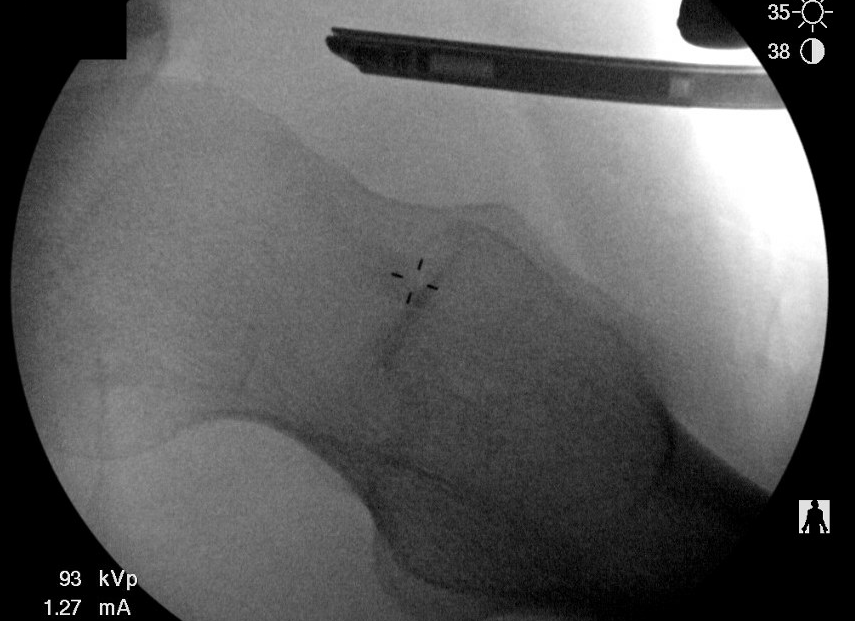

PALA

Insertion of PALA under image intensifier